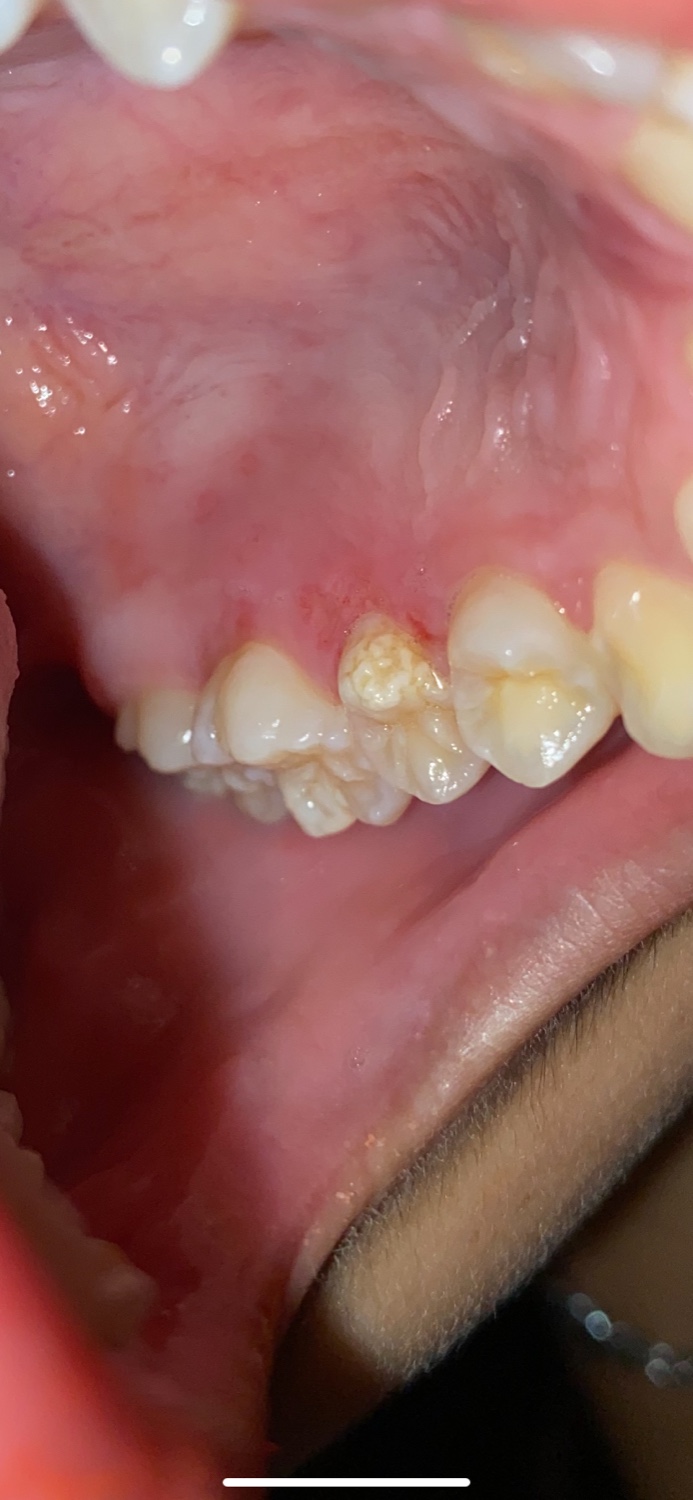

ฟันเป็นแบบนี้ควรไปหาหมอไหมคะ

รู้สึกเจ็บๆเหงือกเลยถ่ายดู ออกมาเป็นงี้ ฟันเป็นหยักๆแบบนี้เขาเรียกว่าอะไรคะ ควรไปหาหมอไหม